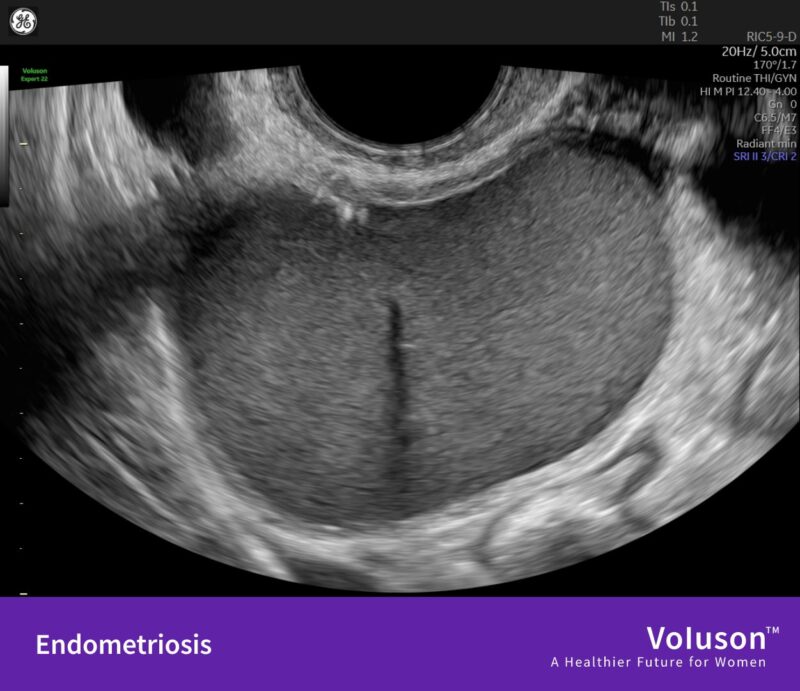

“Similar – but not the same: Adenomyosis vs endometriosis

Adenomyosis and endometriosis share many features – overlapping symptoms, similar impact on patients’ lives, and frequent underdiagnosis.

However, they are two distinct conditions that require different approaches to care.

For endometriosis, ESHRE recommends imaging like ultrasound or MRI as part of the diagnostic workflow.

Swipe through our slides of how adenomyosis and endometriosis might appear in clinical practice!